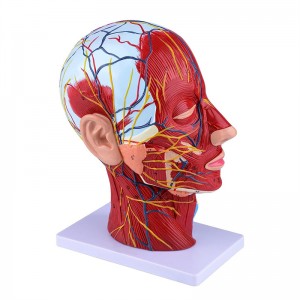

【1: 1 Lifesize】 Sezzjoni medjana ta '1: 1 Natural Head & Neck Mudell tal-muskolu vaskulari newrali superfiċjali (naħa tal-lemin). Xogħol sabiħ. Toffri firxa sħiħa ta 'karatteristiċi anatomiċi.

Dan il-mudell huwa mudell ta 'muskolu newrovaskulari superfiċjali ta' ras u għonq naturali, komponent 1, li juri d-dettalji tar-ras tal-lemin u l-għonq u s-sezzjoni sagittali medjana, inklużi l-muskoli superfiċjali esposti tal-wiċċ, bastimenti superfiċjali tal-wiċċ u l-qorriegħa, in-nervituri u l-istruttura medjali tal-glandola parotida u l-passaġġ respiratorju ta 'fuq, u l-istruttura tas-sezzjoni sagittali tas-sinsla ċervikali